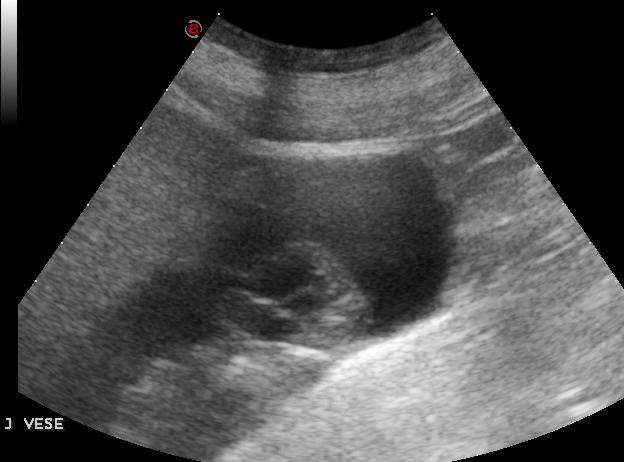

| A jobb vese alsó pólusábn 5 cm-es cystosus képlet, melyen belül vaskos septumok látszanak |